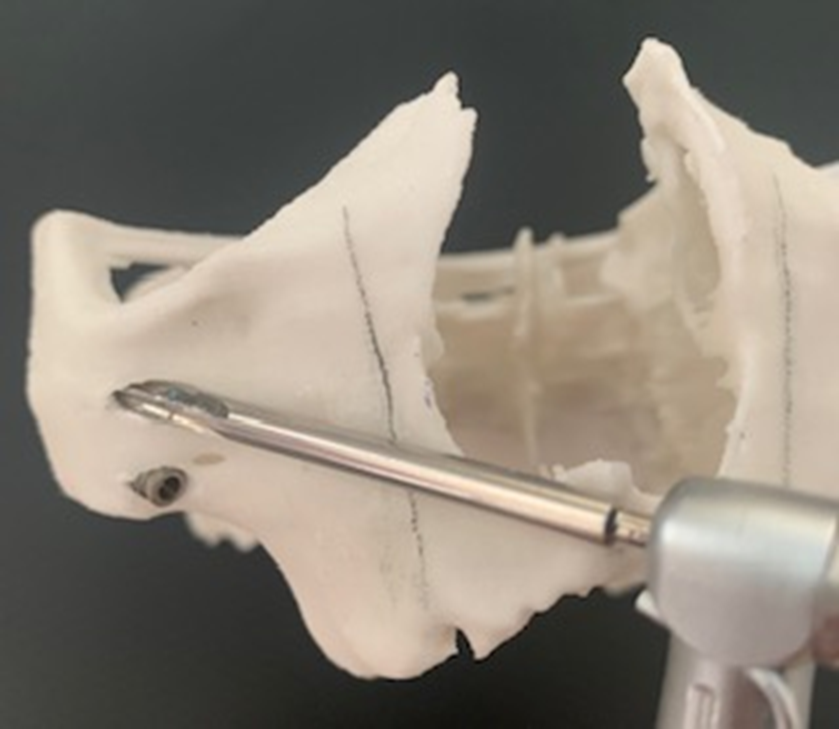

A montagem do Pilar Z exige do cirurgião-dentista habilidade e curva de aprendizado. Nem sempre se consegue adaptar o Pilar Z sem interferências ósseas. Por essa razão, adotamos uma rotina de instalação dos pilares na prototipagem, simulando assim, uma situação muito próxima do real no procedimento cirúrgico.

Desta forma, pode-se observar possíveis contatos ósseos no corpo da maxila ou do zigoma que não permitam o assentamento passivo do Pilar Z.

Conseguimos orientar a plataforma do Pilar Z através da chave de alinhamento, para assentamento passivo da prótese. A visualização do local de emersão do Pilar Z junto ao rebordo alveolar nos indicará onde realizar a osteotomia para confeccionar o “nicho” que abrigará a plataforma do mesmo.